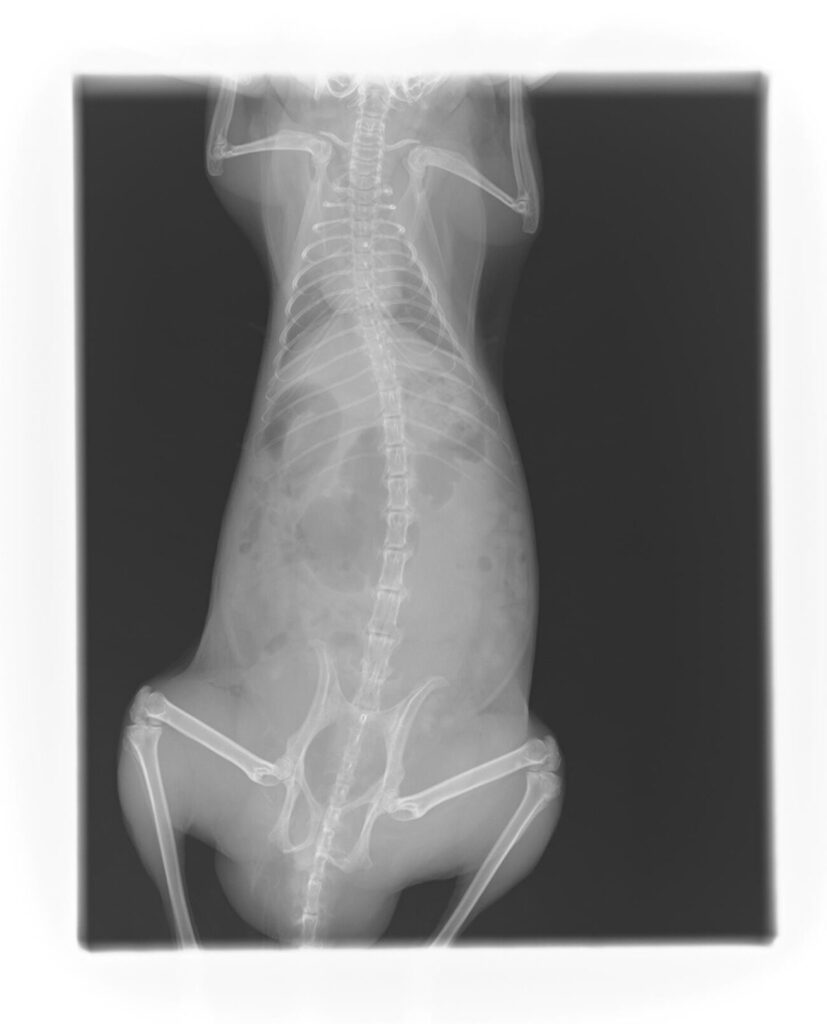

- レントゲン検査

爬虫類(フトアゴヒゲトカゲ)の卵詰まり